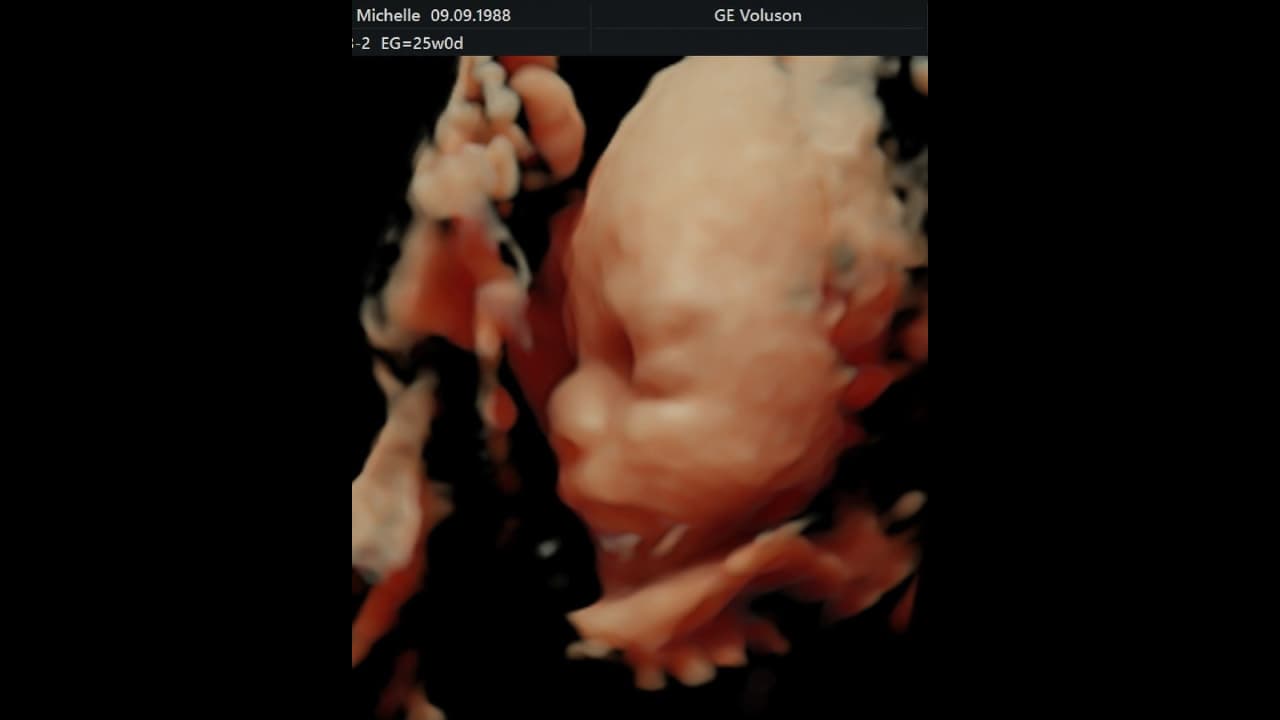

Michelle Renaud atrajo la atención al compartir la primera fotografía de su bebé junto a Matías Novoa. En la imagen, la actriz finalmente mostró la tierna carita de su hijo Milo.

Michelle Renaud deja ver, por fin, la carita de su hijo Milo

Sin embargo, la imagen que cautivó fue en la que mostró la carita de Milo, su segundo bebé. Los fans de la actriz y el protagonista de ‘Marea de pasiones’ opinaron que el bebé “será una belleza” y expresaron su emoción por conocerlo.

“Qué lindas fotos”, “Qué hermosa familia formaron”, “Se parece al papá”, “Tiene tu nariz, se ve”, “Ese bebé estará llenito de amor”, “El bebé será hermoso”, son algunos de los comentarios que le llegaron a Michelle Renaud.